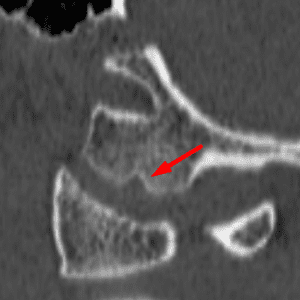

Limbus Vertebra

Mimicking a fracture